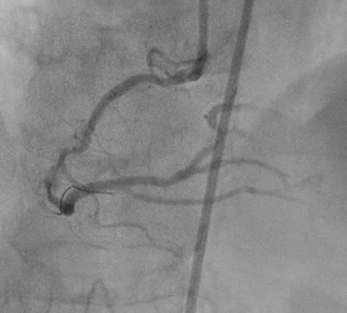

PCI began by engaging a 7Fr JR 4.0 to the RCA ostium via right femoral artery. Wiring initially performed with Runthrough NS through Fine Cross microcatheter, but wire entered subintimal space. Several manipulations to reposition the wire were unsuccessful. Immediate contrast injection showed no flow to the distal part due to abrupt closure of the RCA Patient became angina with marked ST-segment elevation. Rewiring was immediately attempted using Fielder XT-A through Fine Cross microcatheter and the wire successfully entered true lumen A 1.5 x 1.5 mm NC balloon was placed at the lesion but balloon ruptured.A 2.0 x 15 mm NC balloon with extension catheter as support but balloon ruptured.Finally A 2.0 x 20 mm NC scoring balloon successfully inflated then flow was restored with TIMI III flow.Angina relieved, ST-segment lower and hemodynamic improvedIVUS showed massive-compressive intra mural hematoma along distal to proximal RCA with intimal tear of dissection, and the wire within false lumen at mid part RCA.Coronary fenestration attempted using 3.0 x 15 mm NC scoring balloon inflation with dual guidewire inside the lumen.Hematoma surprisingly propagated marked by contrast trapping and no flow to PLBFenestration performed again using 2.5 x 15 mm NC scoring balloon and flow successfully restored.Four DES finally decided to be deployed at distal to ostial RCAFinal angiogram showed excellent result with TIMI III flow, hematoma was disappeared with good stent apposition on IVUS examination